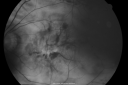

84-year-old woman has polypoidal choroidal vasculopathy in both eyes with macular degeneration. She has macular scars in both eyes and she remains with remarkably good vision in the right eye despite the scarring.

VISUAL ACUITY: OD 20/30, OS 1/200. IOP: OD 13, OS 16. The posterior chamber intraocular lens is in good position in both eyes.

OD: Vertical C/D ratio is 0.2. There is subretinal fibrosis superior, inferior, nasal and temporal to the fovea. The fovea though is relatively spared.

OS: Vertical C/D ratio is 0.2. There is an elevated disciform scar about 8 disc-diameters across, which extends outside the arcades all the way around. Photos confirm clinical findings.

FLUORESCEIN ANGIOGRAPHY: Fluorescein angiography shows irregular hyperfluorescence and staining of subretinal fibrosis, which extends through the fovea. The left eye also has staining subretinal fibrosis. Neither eye has any evidence of any leakage.